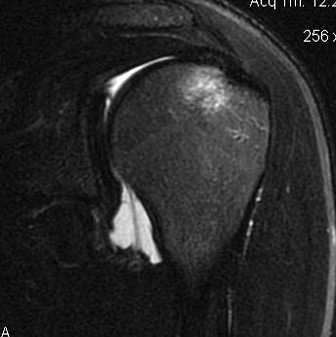

Capsular tears

Clinical

Anterior instability

Intact labrum on MRI

Anterior labrum intact, evidence of capsule tearing + HAGL on MRI